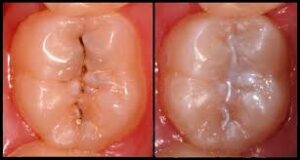

تصویر فیشور سیلانت

تصویر مرحله ای فیشور سیلانت